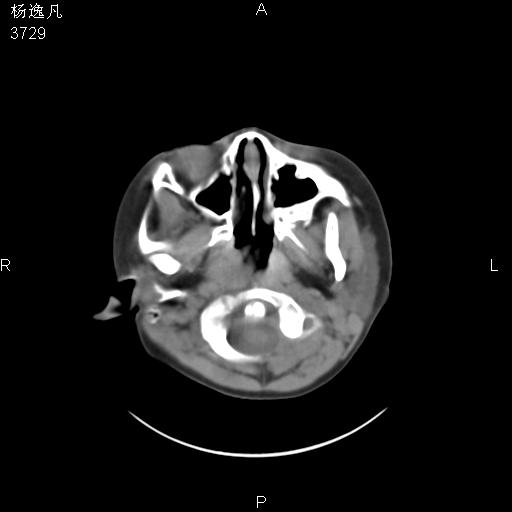

男性,5岁,面部受外伤,余无特殊

鼻咽顶后变窄。顶后壁增厚,考虑腺样体肥大。其它未异常/

头颅ct平扫未见明确外伤性征象,右侧面部及颞部软组织肿胀,后鼻腔软组织影增大,增厚,鼻咽顶部变窄,考虑鼻咽腺样体增值肥厚。

还是重建了再看吧。还可以看一下始矢状位,了解一下气道的情况。